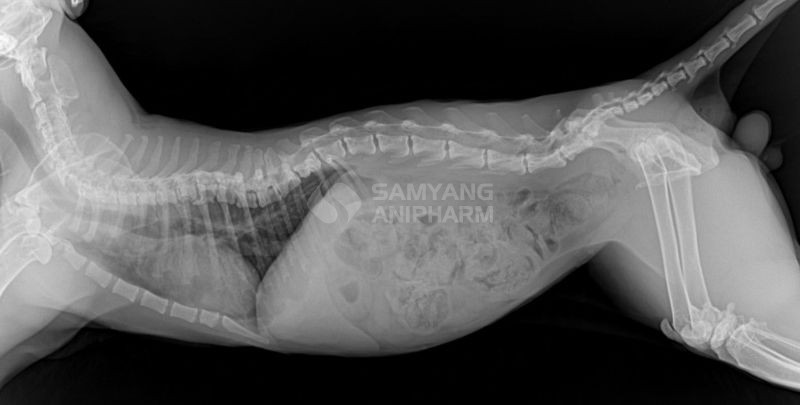

Chó bị thiếu hụt dinh dưỡng bị biến dạng cột sống

- Mất cân bằng Canxi – Phốt pho – Vitamin D: gây ra chứng thiếu xương (Osteopenia) toàn thân, còi xương, khiến xương dễ gãy kể cả xương sống, xương hàm và xương răng gây rụng răng. Ngoài ra, sự mất cân bằng này còn dẫn đến bệnh cường tuyến cận giáp (hyperparathyroidism), teo cơ, liệt, biến dạng cột sống, biến dạng xương sườn làm ảnh hưởng hô hấp.